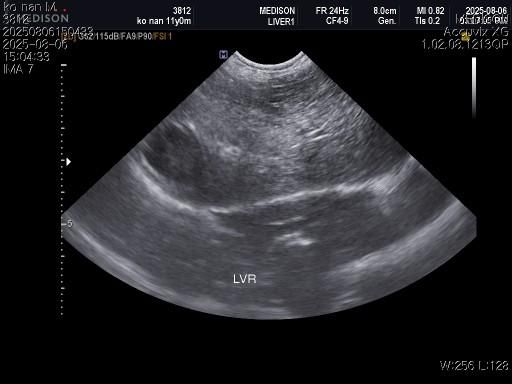

1) 혈액검사와 엑스레이 그리고 초음파상 혈뇨의 원인이 나타나지가 않는지 궁금합니다.

5) 지방간이 있는지 있으면 어느정도인지 궁금합니다..

6) 콜레스트롤과 중성지방이 치료를 들어가야할 정도인지 이것이 혈뇨의 원인인지도 궁금합니다